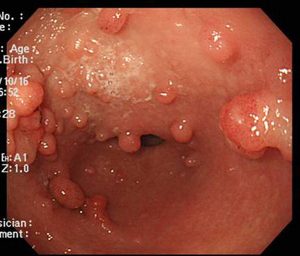

Οι πολύποδες του παχέος εντέρου είναι μία απο τις παθήσεις του παχέος εντέρου εξογκώματα στο έντερο και συγκεκριμένα στο εσωτερικό του παχέος εντέρου (βλεννογόνος). Βλεννογόνος του παχέος εντέρου είναι το εσωτερικό κομμάτι που καλύπτει το παχύ έντερο. Χωρίζονται σε διάφορες κατηγορίες, μια απ’ αυτές είναι σύμφωνα με το μέγεθός τους. Δηλαδή μπορεί να είναι έμμισχοι (θυμίζουν τη μορφή ενός μανιταριού) ή άμισχοι. Σύμφωνα με τα στατιστικά, περίπου το 70% των πολυπόδων είναι ορατοί με το σιγμοειδοσκόπιο (εργαλείο για την εξέταση του παχέος εντέρου). Η αφαίρεσή τους μπορεί να γλιτώσει τον ασθενή από τον καρκίνο σε περίπτωση εξέλιξης των πολυπόδων.

- Αδενωματώδεις πολύποδες (αδενώματα): Οι πιο συχνοί και σημαντικοί λόγω του αυξημένου κινδύνου να εξελιχθούν σε καρκίνο. Οι αδενωματώδεις πολύποδες αποτελούν το 90% των νεοπλαστικών πολυπόδων του παχέος εντέρου και είναι πιο συχνοί στους άνδρες παρά στις γυναίκες.

- Υπερπλαστικοί πολύποδες: Συνήθως μικροί και θεωρούνται κυρίως μη καρκινογόνοι, αν και μεγάλοι υπερπλαστικοί πολύποδες στο δεξιό κόλον μπορεί να χρειάζονται παρακολούθηση.

Κολονοσκόπησης: Η κολονοσκόπηση εξασφαλίζει άμεση και λεπτομερή επισκόπηση του εσωτερικού του παχέος εντέρου, καθώς και την αφαίρεση των πολυπόδων που ενδεχομένως να έχουν αναπτυχθεί. Αυτή η διαδικασία είναι πολύ σημαντική για την πρώιμη διάγνωση και την πρόληψη σοβαρών καταστάσεων.

Οι πολύποδες παχέος εντέρου και συγκεκριμένα η αφαίρεση τους γίνεται συνήθως κατά τη διάρκεια της κολονοσκόπησης, ενώ για μεγαλύτερους πολύποδες παχέος εντέρου μπορεί να απαιτηθεί εξειδικευμένη και πιο προηγμένη τεχνική, ώστε να διασφαλιστεί η πλήρης και ασφαλής αφαίρεση τους.